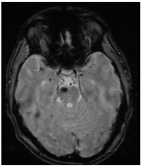

The reported incidence of first hemorrhage in prospective studies ranges from 0.1 to 2.7 lesions per year [17,26,27]. According to the meta-analysis by Horne et al., the pooled annual risk of hemorrhage is approximately 2.4% for all CMs and 4.5% for previously hemorrhagic lesions [28]. Natural history studies suggest an annual hemorrhage risk of 2.3–4.1% for CMs, whereas surgical series report 2.7–6.8% annually before intervention [9,29,30,31]. Incidentally identified CMs have a lower first-hemorrhage risk (0.08% per person-year) [32,33]. A first hemorrhage may destabilize a CM, increasing the risk of subsequent bleeding, with rebleeding rates estimated between 4.5% and 34% per year. The cumulative incidence of rebleed is 56% at five years and 72% at ten years [26,27,29,30,31,32]. Kondziolka et al. reported hemorrhagic rates of 0.6% for incidentally discovered CMs, 4.5% after one hemorrhage, and 32% after more than one [33]. The most consistently identified risk factors for bleeding are brainstem location and prior hemorrhage. Other putative factors, identified in some, but not all studies, include female sex, the presence of a DVA or a DVA–CM complex, larger lesion size, and persistent or new T1 hyperintensity on MRI [17,18,19,20,21,22,23,24,28,30]. CMs located in the brainstem and thalamus/basal ganglia have higher risks of initial and recurrent hemorrhage (2.3–8.7% for first events, 12–60% for recurrences) and greater persistent morbidity after a single hemorrhage (40–60%), with cumulative disability increasing after subsequent events [28,30,32]. On the other hand, superficial CMs more frequently cause epileptic seizures after the initial hemorrhage, whereas focal neurological deficits are less common [26,28,30]. Rebleeding occurs in approximately 40% of CM remnants post-surgery, highlighting the need for early postoperative MRI within 72 h, with consideration for reoperation if substantial residual lesions are present (Figure 3). Rebleeding risk may be time-dependent, increasing for at least five years after the initial hemorrhage and declining thereafter, particularly in women [34]. This “temporal clustering” can affect the interpretation of treatment efficacy, especially following SRS. However, not all natural history studies have confirmed a reduction in risk after five years, and some report a persistently elevated or fluctuating hemorrhage rate over time [27,29]. Reported cumulative rebleeding rates are approximately 14% within the first year and 56% within five years [30,35,36].